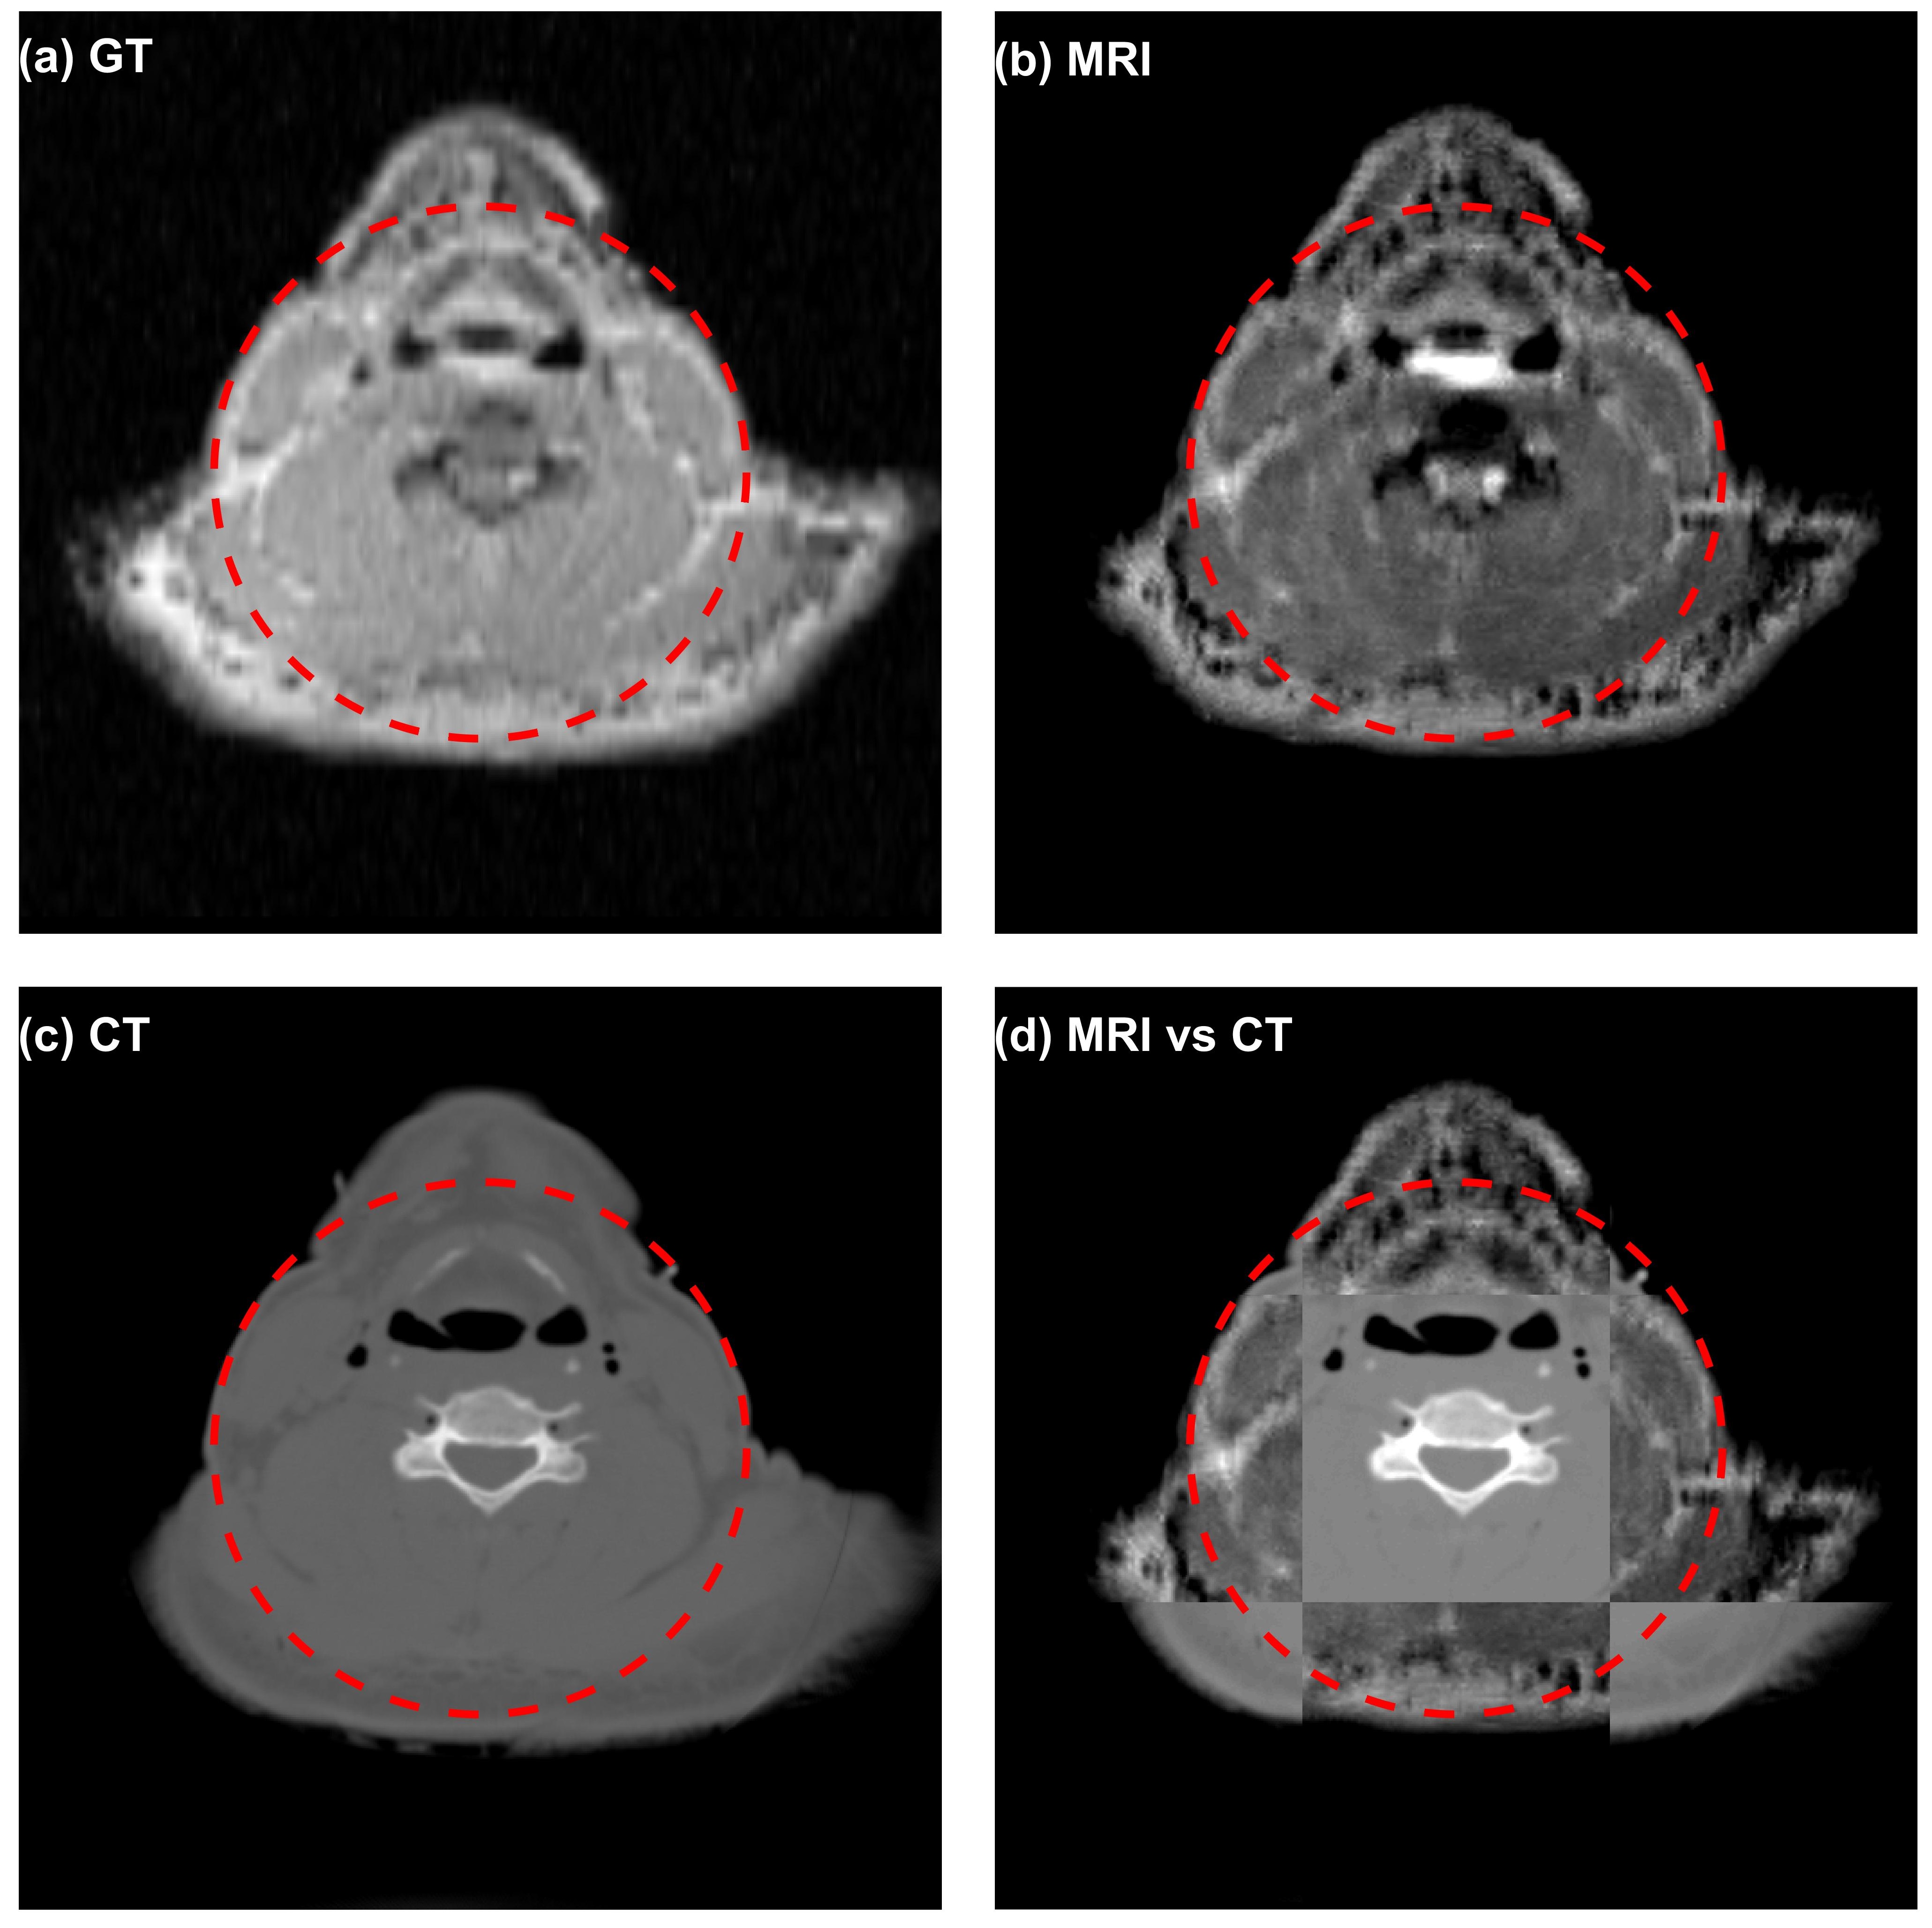

We present in Figures 7 and 8 the results from the neck and chest sites. In each figure, in addition to presenting the simulation results of the CT and MR images, we also generated a blended view by displaying CT and MRI images in different squares. The capability of integrated CT-MRI imaging in the same spatial coordinate system is expected to offer advantages in a variety of clinical tasks, such as disease diagnosis and therapy planning.

Figure 7: Axial planes of (a) proton density image of the VHP neck phantom, (b) simulated MR image (TR=1,000 ms,TE=80 ms, and NEX=16), (c) simulated CT image, and (d) blended view of MRI and CT images. The dashed red circles indicate the targeted FOV of 15 cm in diameter.

Figure 8: Axial planes of (a) proton density image of the VHP chest phantom, (b) simulated MR image (TR=1,000 ms,TE=80 ms, and NEX=16), (c) simulated CT image, and (d) blended view of MRI and CT images. The dashed red circles indicate the targeted FOV of 15 cm in diameter.